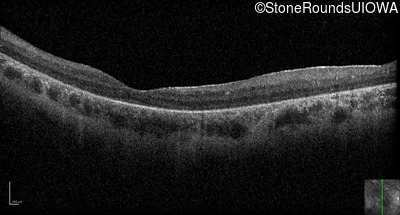

Optical Coherence Tomography - Left - 10/350 sc

Exemplar / OCT Stack